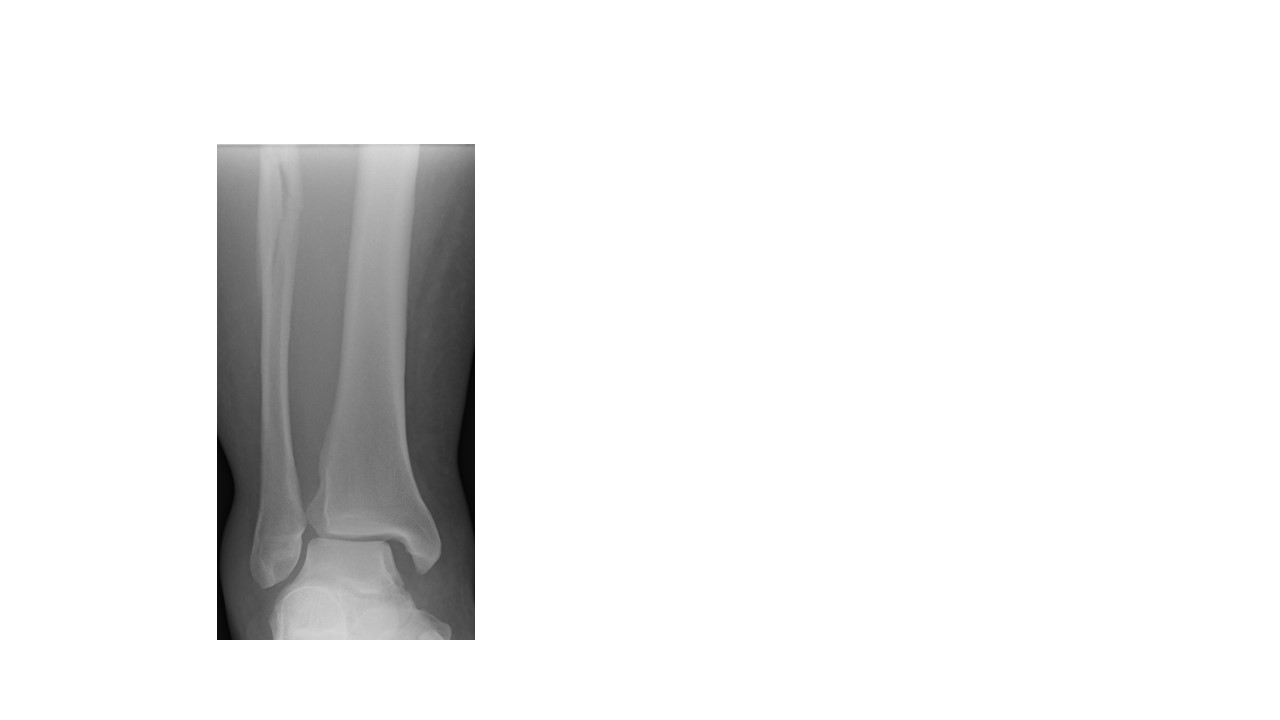

We employ our experience as well as established normal reference values on plain X-ray. These will help determine whether there is an obvious syndesmosis injury or highlight a particular fracture pattern that is highly predictive of a syndesmosis injury such as the high fibular fracture ( a “Maisonneuve injury”) above the ankle syndesmosis (shown below).